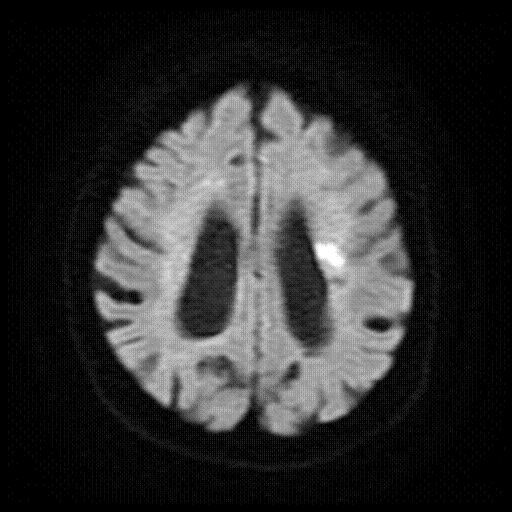

(4)1.5T MRI検査

MRI検査は磁場と電磁波を用いて様々な断面を撮影できる装置を使った検査です。放射線を用いないため、被曝はありません。撮影中大きな音がしますが、ヘッドホンなどで軽減させる等工夫をしています。強い磁力の中での撮影になるため、体内にペースメーカーや金属が入っている方は検査できないことがあります。また、時計・磁気カード・電子機器などは故障の恐れがあるため持ち込めません。

(GE社製 Signa HDxt optima edition)